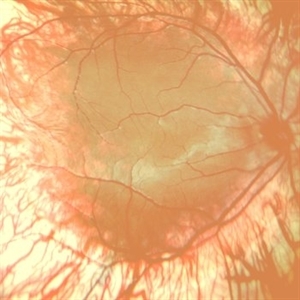

AMBLYOPIA

COLOUR FUNDUS PHOTOGRAPH OF A 12 YEAR OLD MALE CHILD WITH HIGH REFRACTIVE ERROR WITH AMBLYOPIA

Photographer: Dr. Akansha Sharma-Retina Foundation, Ahmedabad

Condition/keywords: amblyopia